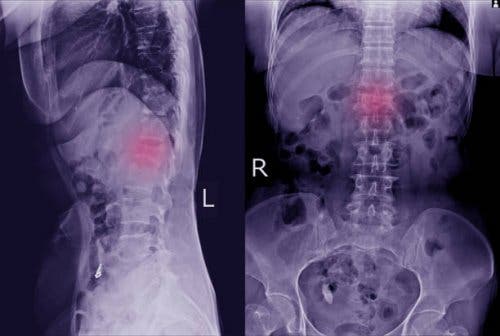

These physical manifestations are easy to overlook. However, paying attention to them will allow you to go to the doctor to perform one of the main tests that will allow their detection: x-rays. That way, it’ll be possible to see clearly if there’s a displaced vertebra.

In some cases, the doctor may require more specific tests, such as a computerized topography or an MRI scan. With these additional tests they can see more clearly if there’s spondylolisthesis and also if it has affected bones and nerves.